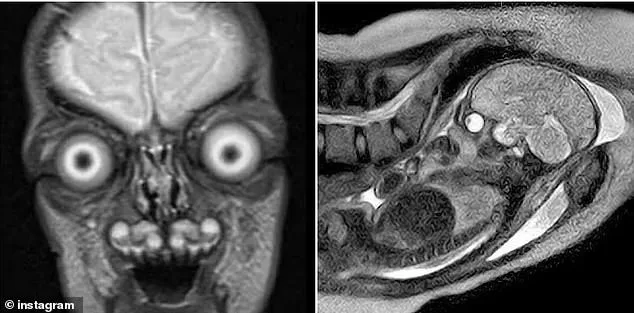

Disturbing images of fetal MRIs have resurfaced online, sparking renewed debate about the safety and necessity of the procedure during pregnancy. These scans reveal an unsettlingly clear view of a fetus's anatomy, with bones appearing as stark white against darker tissue. The skeletal structure, including the spine, ribs, skull, and even individual finger bones, stands out in sharp detail. Eyes, filled with fluid, appear as dark, hollow sockets that sometimes seem to bulge or stare outward, evoking a sense of eerie realism. For expectant mothers, such images can be profoundly unsettling, raising concerns about potential risks and long-term effects.

MRIs for pregnant women typically occur when there is a need to investigate life-threatening conditions such as tumors, congenital disorders, or joint abnormalities. Unlike ultrasounds, MRIs involve lying in a narrow tube, which can induce claustrophobia, especially in the third trimester. Positioning is also challenging due to the risk of compressing major blood vessels when lying flat. These physical discomforts add to the psychological strain for many women, who may already be anxious about the procedure.

Public reactions to shared MRI images often range from fascination to fear. Online commenters have described the scans as both terrifying and strangely captivating, with some users expressing disbelief at the images' realism. Yet despite these mixed reactions, data from a 2023 study of 156 pregnant women reveals a significant willingness to undergo MRIs when medically indicated. Eighty percent of participants would opt for an MRI if prescribed by a doctor to diagnose a potential issue, but only 24 percent were open to participating in MRI research. This highlights a clear divide in public perception, with most women prioritizing medical necessity over curiosity.